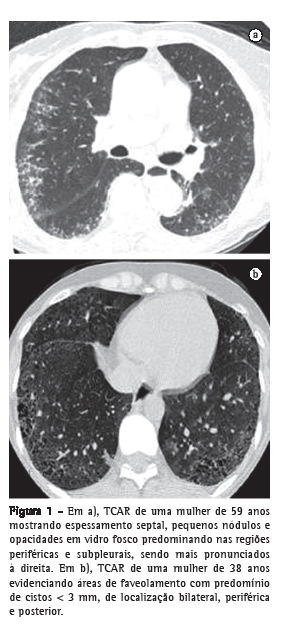

b) TCAR realizada com um aparelho GE (modelo HiSpeed LX/i; General Electric Medical Systems, Milwaukee, WI, EUA), com cortes com espessura de 1,0 mm, intervalo de tempo de 1,5 s, incremento de 10 mm, reconstrução de imagens com matriz de 512 × 512 pontos com algoritmo de alta resolução, largura de janela de 1.000 UH e nível médio de janela de −700 UH. A interpretação dos achados tomográficos foi feita de maneira independente por dois radiologistas com experiência em doença intersticial pulmonar. A TCAR foi analisada procurando-se os seguintes achados: pequenos nódulos, opacidade em vidro fosco, espessamento septal, faveolamento e bronquiectasia de tração. Para fins comparativos, os pacientes foram divididos em dois grupos, de acordo com a presença ou não de faveolamento (Figura 1).

Não houve discordância entre os radiologistas quanto à presença ou ausência de pneumonia intersticial, nem quanto aos achados tomográficos diagnosticados. As principais anormalidades tomográficas foram pequenos nódulos (opacidades arredondadas < 1 cm), espessamento septal e opacidades em vidro fosco, detectados em 30, 29 e 26 casos, respectivamente. O aspecto de favo de mel foi notado em 17 casos, sendo que, em 13 deles, havia áreas de vidro fosco pouco extenso de permeio. Bronquiectasias de tração foram observadas em 13 casos, todos eles com áreas de faveolamento associadas.